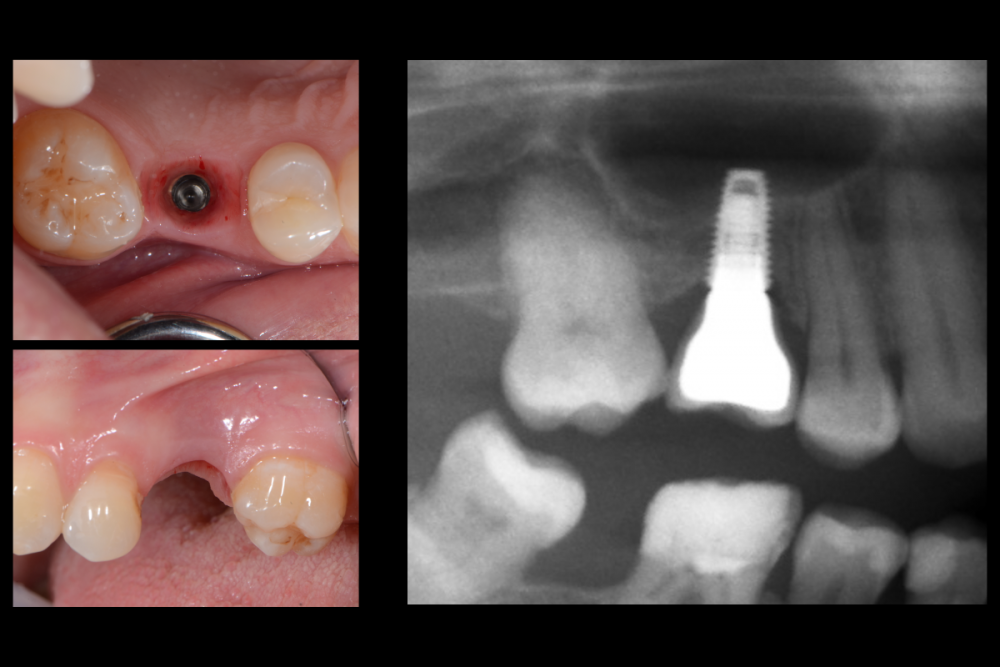

Карен Аванесов Опубликовано 10 июля, 2021 Поделиться Опубликовано 10 июля, 2021 В одноимённой теме топикстартера Женьки (Евгений неплохой человек, культурный, не хамит, а профессиональная уверенность придет с опытом, выше нос!), так вот, я высказал свое решение для реализации клинической ситуации. Это не уникальная ситуация и на мой взгляд не требует усложнений, усложнений именно для того что бы кому-то подражать, повторять, а ориентироваться надо на пожелания пациентов исходя в том числе из финансовой составляющей (я не буду гнать пациента за кредитом в банк на унитазный инстаграмный забор что бы быть "своим" среди чужих, да конечно, я лох, но если где-то в магазине подкованный на курсах по продажам консультант-менеджер, в не свежей рубашке, с грязными коготками, начнет меня уговаривать в свою сторону, на то что мне не нужно, я приобниму его нежно за ягодицы и уйду)) Так же, учитывать общую клиническую ситуацию, куда "прописываются" новые зубы. Кстати про финансовую составляющую, если просто стараться, без адекватной отдачи, ждет профессиональное выгорание и деформация, об этом стоит помнить. Итак, представленной работе 5.5 лет Пациент получил то что хотел и доволен, жалоб нет, доволен ли я? Да я доволен! По кейсу, все видно на фотографиях, время работы 30 минут имплантаты 3.6 х8, 3,6 х10 (да, сейчас совсем коротышки бы установил), но несмотря на все мои потуги, думаю что бикортикально все же, а не как бэ закрытый синус лифтинг. 6 1 Ссылка на комментарий

Женька Опубликовано 10 июля, 2021 Поделиться Опубликовано 10 июля, 2021 Карен, вы не неправильно (возможно) меня поняли. Усложнял я свой кейс не намерено, и не потому, что у кого-то увидел в соц сетях. А банально потому, что опыта нет, и в тот объём который был у меня (мне кажется он всё-таки меньше чем у вас) я просто побоялся поставить имплантат. Спасибо, что поделились! Ремоделировка конечно приличная даже с учётом заглубления хорошего (я не критикую, лишь говорю что вижу), но за 5.5 лет никаких проблем, значит и дальше будет хорошо. Если вы не против, я могу выслать КТ в личку, там и побеседуем, что скажете? Ссылка на комментарий

Карен Аванесов Опубликовано 10 июля, 2021 Автор Поделиться Опубликовано 10 июля, 2021 9 минут назад, Женька сказал: Карен, вы не неправильно (возможно) меня поняли. Усложнял я свой кейс не намерено, и не потому, что у кого-то увидел в соц сетях. А банально потому, что опыта нет, и в тот объём который был у меня (мне кажется он всё-таки меньше чем у вас) я просто побоялся поставить имплантат. Спасибо, что поделились! Ремоделировка конечно приличная даже с учётом заглубления хорошего (я не критикую, лишь говорю что вижу), но за 5.5 лет никаких проблем, значит и дальше будет хорошо. Если вы не против, я могу выслать КТ в личку, там и побеседуем, что скажете? Ремоделировка, да не красиво, не критично и в большей степени связана с бездумной технической работой, слава Богу я больше не работаю с этой лабораторией и очень стыдно, что рекомендовал ее коллегам. Ссылка на комментарий

Карен Аванесов Опубликовано 16 июля, 2021 Автор Поделиться Опубликовано 16 июля, 2021 14.07.2021 в 16:45, Марья Моревна сказал: А позвольте Вас спросить, Карен, сейчас какие коротышки бы Вы установили вместо 3,6 x 8,0 в этой ситуации? 4Х7мм, диаметр 3.6 несколько лет как перестал применять, не вижу в них смысла. 1 Ссылка на комментарий